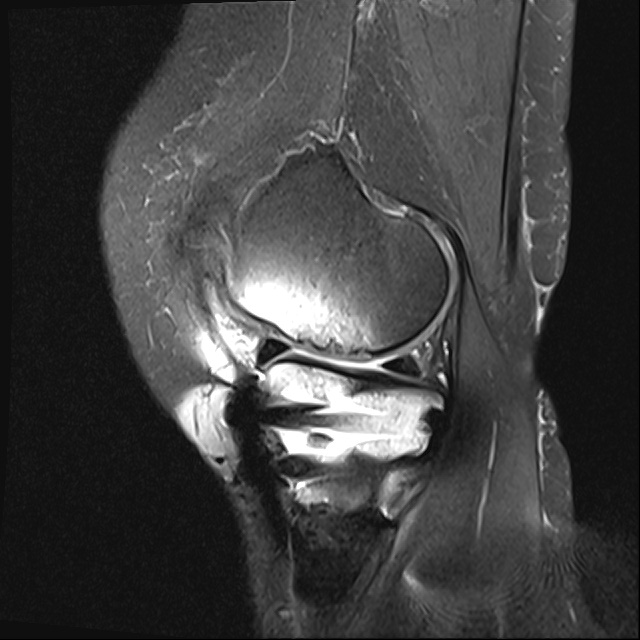

수술 후 MRI

2022.10.25